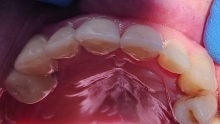

Pot folosi aparate dentare si adultii, deoarece reprezinta cea mai buna varianta de indreptare a problemelor prezente la nivelul cavitatii orale, dar si de natura estetica. Medicul ortodont recomanda aparate dentare in urmatoarele cazuri: dinti strambi sau inghesuiti, dantura cu multe spatii, persoanele care au diastema (strungareata), dificultati la mestecarea alimentelor.

De cele mai multe ori este nevoie ca dispozitivele ortodontice sa fie purtate intre 6 – 24 luni. Aparatul dentar poate preveni aparitia gingivitei dar si cariile dentare. Dintii strambi si nealineati corespunzator sunt foarte greu de curatat. O igiena dentara incorecta duce la aparitia cariilor.

Exista mai multe tipuri de aparate denatare: metalic, ceramic, lingual (invizibil) etc.